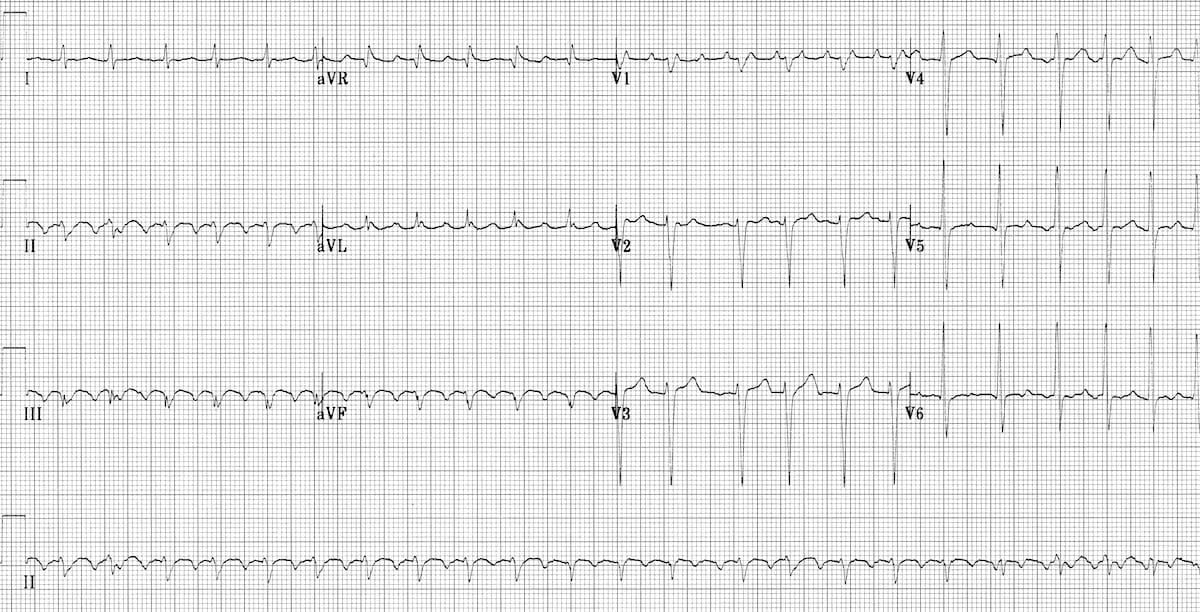

This ECG shows features suggestive of PE. Sinus tachycardia is present (rate 100 bpm). There is clear T wave inversion in right precordial leads (V1-V4) and in inferior leads (II, III, aVF). S1Q3T3 pattern is also present.